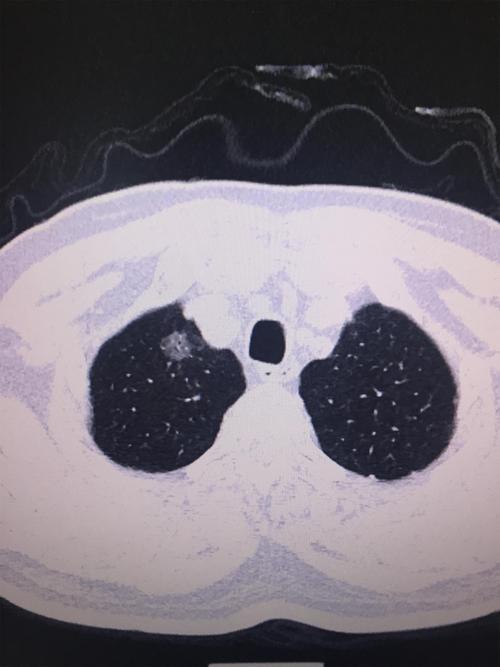

弄清楚良性结节饮食上注意什么之前,先要弄清楚良性结节是什么?良性结节,前面科普文章也多次描述,多数为肺内淋巴结影,炎症瘢痕灶,炎症病灶、包括腺瘤样增生。如果是肺内淋巴结影,多数是过去感染过结核、炎症等,使得局部淋巴结增大。炎症瘢痕灶,就如同你体表皮肤上,可能会有很多几毫米到几厘米的瘢痕。这两个是不会给人体造成不适和危害。如下图:

此外,还有一些随访中的5mm磨玻璃结节,考虑有可能是良性阶段的腺瘤样增生(如下图),这里面有一部分可能会随着时间的推移,变成原位腺癌、微浸润腺癌,也有一部分可能一辈子都不会变化。目前没有任何证据说什么饮食可以使这种腺瘤样增生磨玻璃结节增大、或者消失。这种磨玻璃结节变化非常缓慢,倍增时间甚至要10年,只要做到定期复查,肯定是安全的。